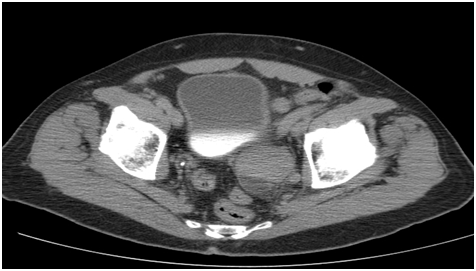

The patient is a 63 year-old male diagnosed in February 2010 with transitional cell bladder carcinoma located at the left posterior ureterovesical junction. The initial CT scan showed the tumor measured 3.91 cm in its posterior to anterior diameter (Figure 2). A plant-derived extract called Salicinium, which is thought to be selectively toxic for cancer cells, was prescribed by his physician. By 3 months, however, the tumor had grown to approximately 7 cm x 4 cm, with compression of the bladder wall (Figure 3). The patient’s physician then decided to try intravenous Enercel. The patient gained symptomatic relief and over the next 2 weeks reported passing blood and tissue pieces in his urine. After 12 weeks of Enercel therapy the tumor had decreased back to 4.01 cm in its widest diameter and was no longer compressing the bladder (Figure 4). The volume of the tumor since beginning of the Enercel therapy was estimated to have decreased by 53%. Hypodense areas were seen inside and along the edges of the mass consistent with tumor cell necrosis. Symptomatically, the patient reported feeling much improved in his overall health. Rather than continuing with Enercel, the patient opted to travel to Mexico for stem cells, catheter administration of supplements and attempted catheter removal of residual tumor. These endeavors led to Pseudomonas aeruginosa sepsis that failed to respond to months of antibiotic therapy. Surgery was finally attempted but failed and the patient died. The case is informative, however by the Enercel induced a significant reduction in tumor size (7 cm versus 4 cm largest diameter) and the clinical and radiological evidence of apparent tumor necrosis.

Figure 2 A CT scan of the pelvis at the time of presentation (2-19-2010). It shows a mass at the left posterior ureterovesical junction that measured 39.1 mm in its widest diameter. The patient began taking Salicinium, a plant derived compound reportedly selectively toxic for tumor cells.